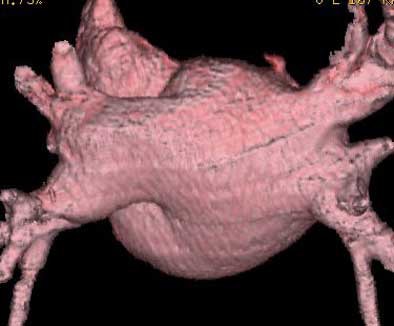

![]() |

| Endocardial (above) and epicardial (below) views from a patient with an accessory vein on the right (which happened to be vein that drained the right middle lobe (RML) and superior segment right-lower lobe (ssRLL), as well as separate LS and LI veins (left side seen in epicardial view only), for a total of five pulmonary veins. Images courtesy of Dr. Joan Lacomis. |

Epicardial volume-rendered views should include the left atrium and the distal third of the pulmonary veins, but not the heart, pulmonary arteries, aorta, or vena cavae, in order to show the relevant structures without their being obscured by the adjacent anatomy.

"On the posterior (epicardial) view you can see clearly four pulmonary veins on this patient," she said. "We can look for ostial branches (defined as branches that join the main pulmonary trunk within 5 mm of the AV junction). And as we rotate this left atrium around, we really get a good feel for local LA size and shape."